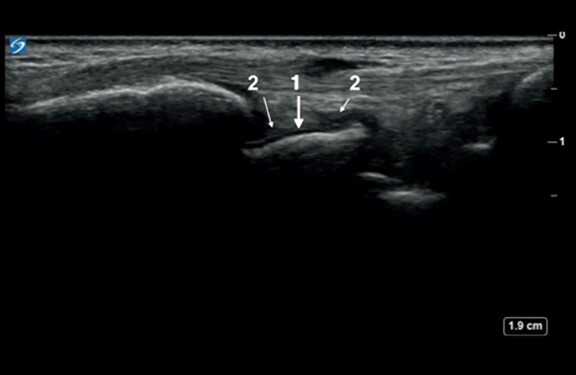

1. Hyaline Cartilage of the Scaphoid

2. Normal Amount of Synovial Fluid